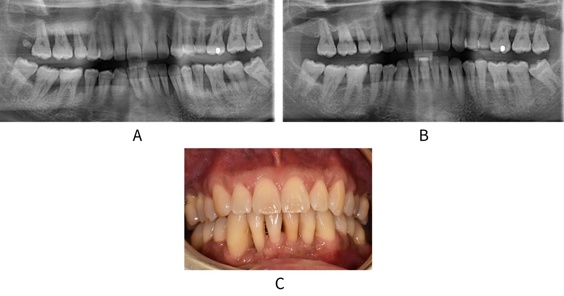

Image A shows a baseline radiograph for a 40-year old patient with Stage IV periodontitis. Image B shows a radiograph following 5 years of non-surgical treatment and supportive therapy. Note the bone healing, particularly in the lower right quadrant. Image C shows a clinical view of this patient at 5 years. Despite the extensive recession in the lower anterior region, there is no gingival inflammation and the level of oral hygiene is excellent. This patient had been a smoker at initial presentation and managed to successfully quit.